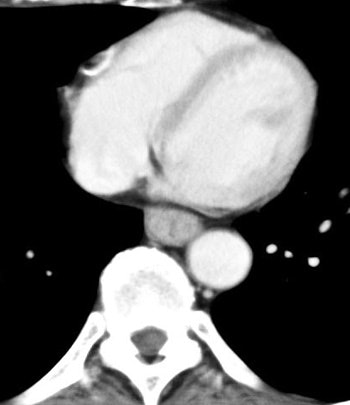

![]() |

| Venous-phase image of a 60-year-old male with stage T1b esophageal cancer. The tumor cannot be seen in the venous phase. |